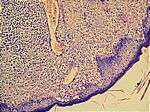

Mycosis fungoides, HE/Giemsa